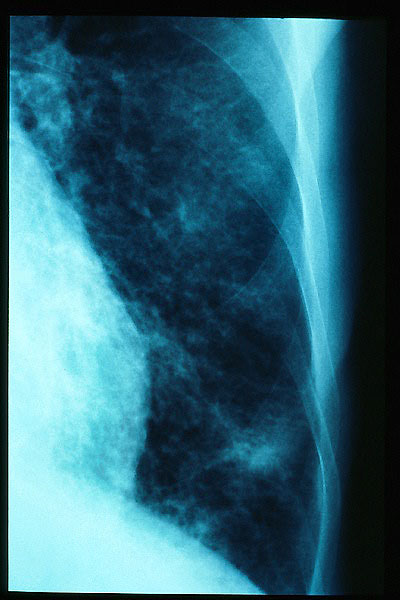

TBC pulmonar antigua